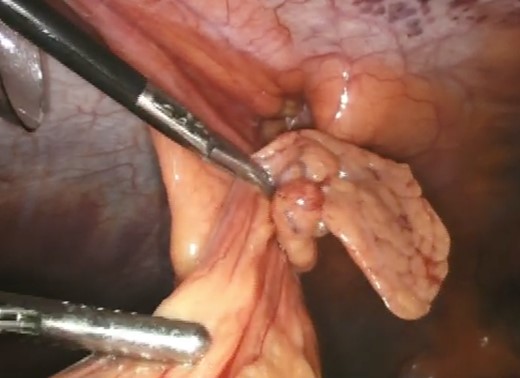

A computerized tomography (CT) scan demonstrated a chronic ventral hernia (Fig. 1) containing fat anterior to the left lobe of the liver which had marginally increased in size from a previous study done a year earlier. Through judicious use of analgesia, the hernia was successfully reduced. Two weeks later, the patient underwent a laparoscopic transabdominal pre-peritoneal (TAPP) mesh repair (Fig. 2). Laparoscopic visualization revealed, along with viable incarcerated omentum (Fig. 3), a falciform ligament hernia extending into the abdominal wall in the epigastrium.

Incarcerated omentum (green arrow) within the falciform ligament (black arrow).